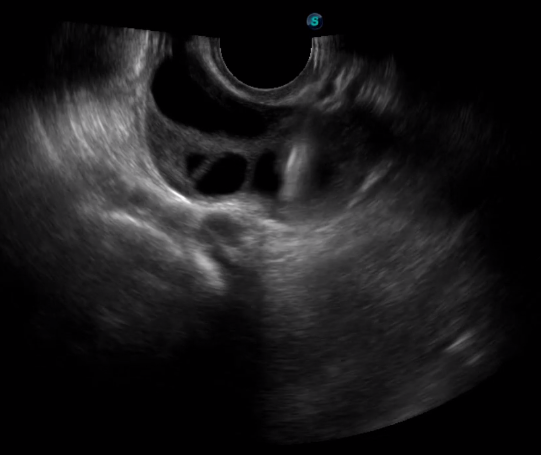

1生殖專用探頭

傳統(tǒng)腔內(nèi)探頭采用直柄設(shè)計,在搭配穿刺架使用時,手術(shù)空間小,不易操作;生殖專用的曲柄探頭,探頭柄采用彎曲成角度設(shè)計,可實現(xiàn)監(jiān)視、取卵兩不誤,搭載穿刺架時,可以清晰顯示穿刺針的進(jìn)針過程、深度和位置,實時監(jiān)視取卵全過程,保障取卵操作精準(zhǔn)與安全。

取卵臨床圖